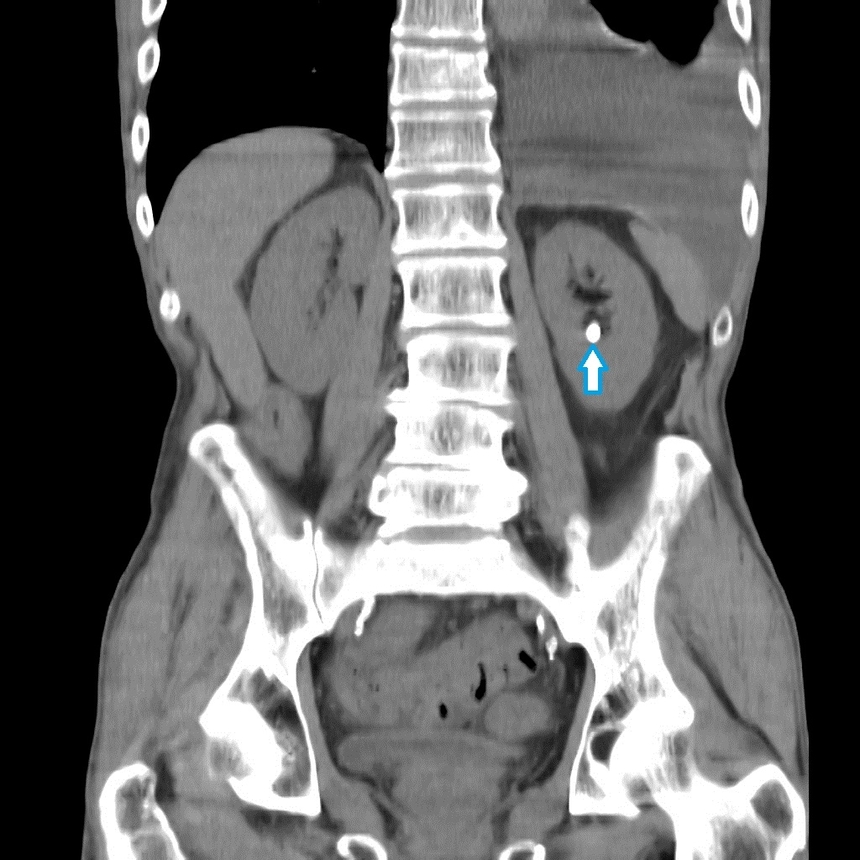

При неоперабельных случаях используется постановка стента в мочеточник, который выполняет роль обходного шунта, по которому происходит отток мочи из почки в мочевой пузырь. Но необходимо помнить, что подобная операция является всего лишь симптоматической и не способная полностью излечить больного. Примерно раз в месяц больной нуждается в замене стента. Стоит отметить, что процедура довольно неприятная и болезненная.